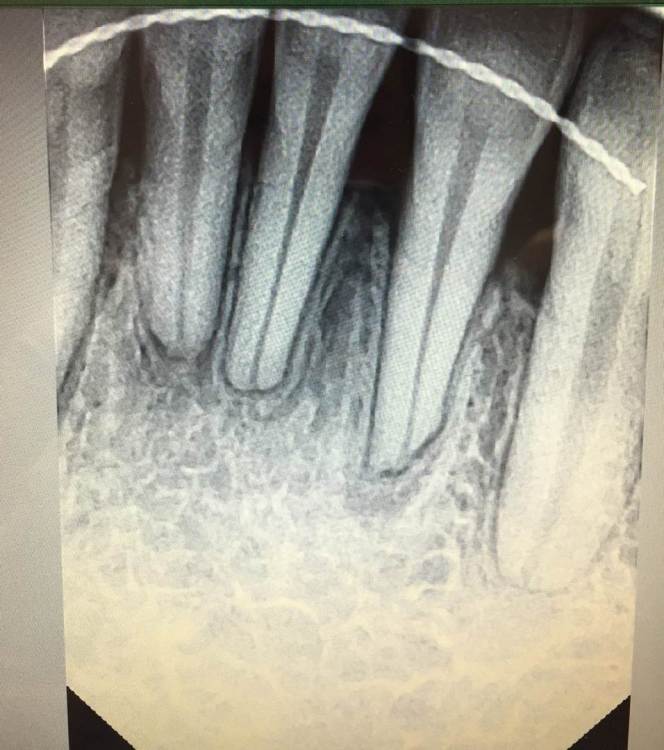

Уважаемые специалисты, прошло 5 месяцев после снятия брекетов, была у терапевта, лечила зуб и случайно на снимок попала область передних резцов, пересняли прицельно. Моего терапевта смутило состояние кости. Ортодонт говорит, что это нормально  после лечения и оценивать надо не меньше чем через год после окончания. Но все равно есть переживания.. Подскажите нормально ли это?